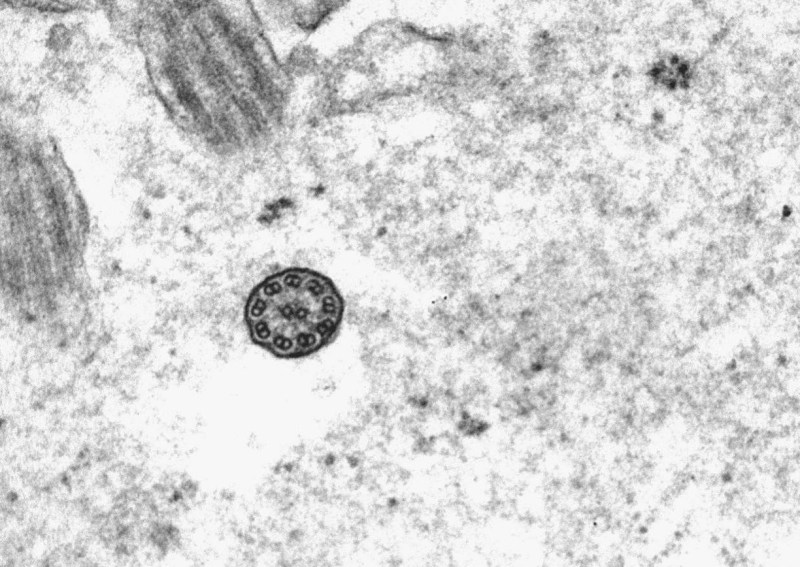

Ultrastructural Findings

- >50 mid-shaft cilia are examined.